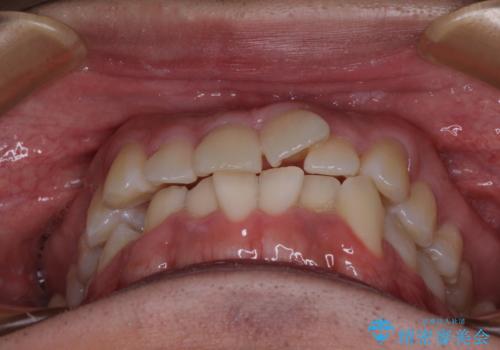

前方に捻れた前歯を治したい インビザライン矯正治療

- 前歯のデコボコを治したいとのことで来院された患者様です。

上下顎ともに歯列全体の後方移動とIPR(歯と歯の間を削る)によってデコボコが解消するように設計し、インビザラインにより治療を行うこととしました。

下顎前歯は後戻りを起こしやすいため、舌側を細いワイヤーで固定し、マウスピース型リテーナーで保定を行うこととしました。